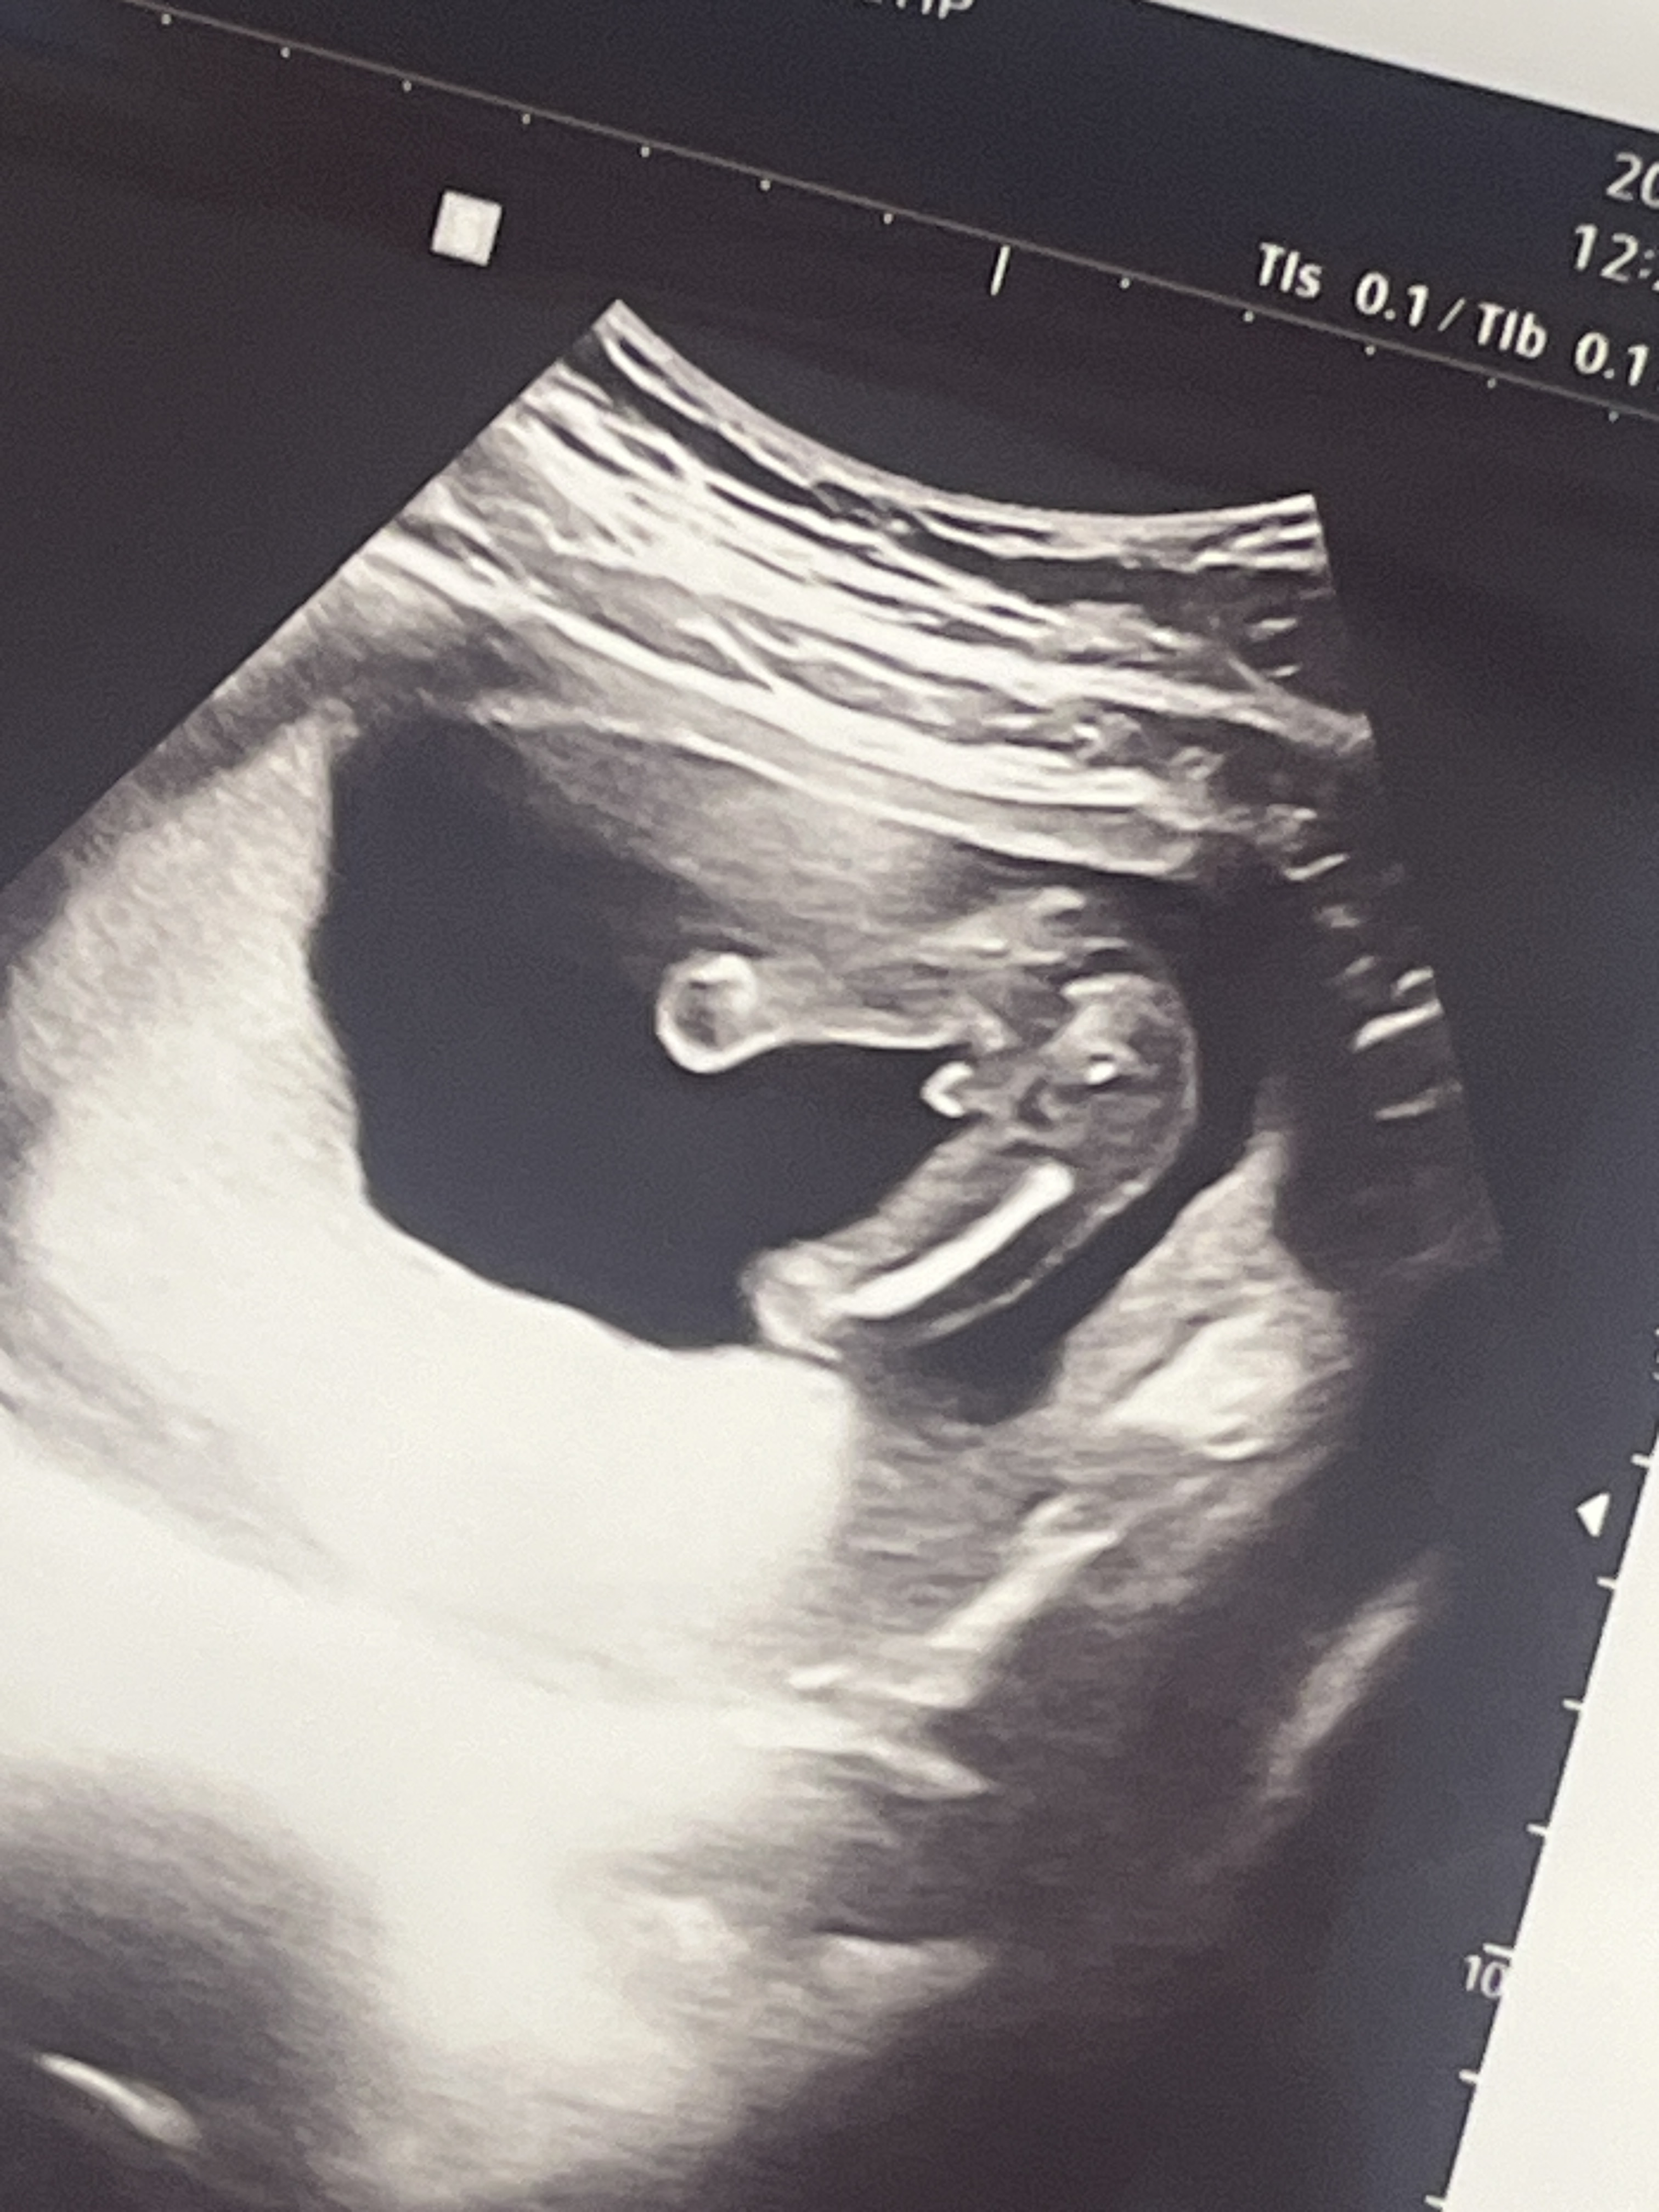

16주 차 2차 기형아검사를 하러 갔더니 고추가 딱!!!!!!!!!!!

어어.,.? 딸이라고 했는데요? 했더니 고추가 이렇게 있다고... 아들이라고...

정말 놀랍게도 장꾸맘 각도법이 맞았고 병원에서 틀렸어요...

제가 본 각도법도 딸인 줄 알았는데 정말 어떤 눈을 가지신 건가요!!!!